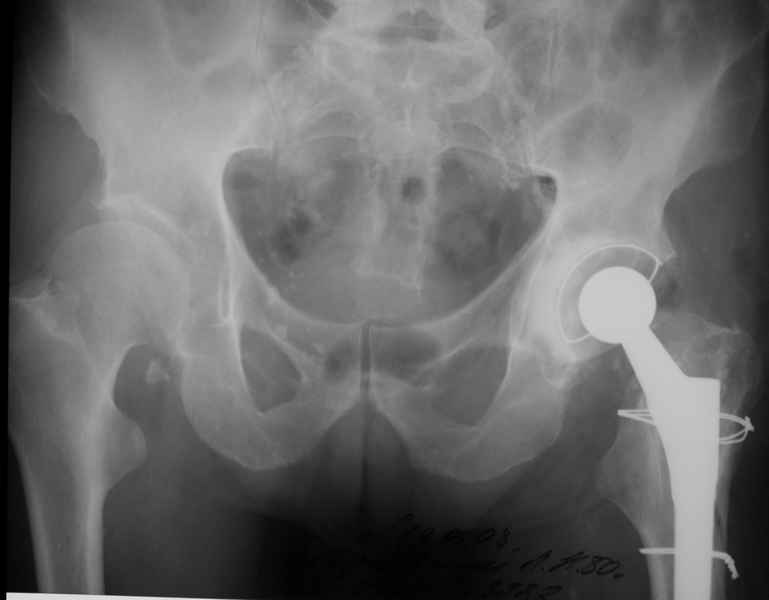

Уважаемые коллеги, продолжая дискуссию, начатую на "Вреденовских чтениях", хочу сказать, что принципиально сущестует два возможных варианта лечения.

1.Остеосинтез на ножке. Мне кажется, что применительно к этому случаю малоперспективный вариант. Синтез хорош, когда можно его выполнить в малоинвазивном исполнении и достигнуть стабильности. Действительно, если ножка б/цементной фиксации после этого не будет иметь фиксации, то ревизия не будет иметь проблем. В представленном случае стабильность синтеза сомнительная, а проведение доп.иммобилизации приведет к контрактуре суставов.

2. Применение ножки дистальной фиксации, мы отдаем предпочтение ножке Вагнера с фиксацией проксимального отдела на ножке. Более травматичное вмешательство, но при стабильной фиксации ножки реабилитация идет в обычном режиме.

Хочется показать два подобных случая, П-ка З. 72 лет и п-т Г. 80 лет. Сразу принимаю замечание, что это были ножки цементной фиксации, просто под руками не было бесцементника.